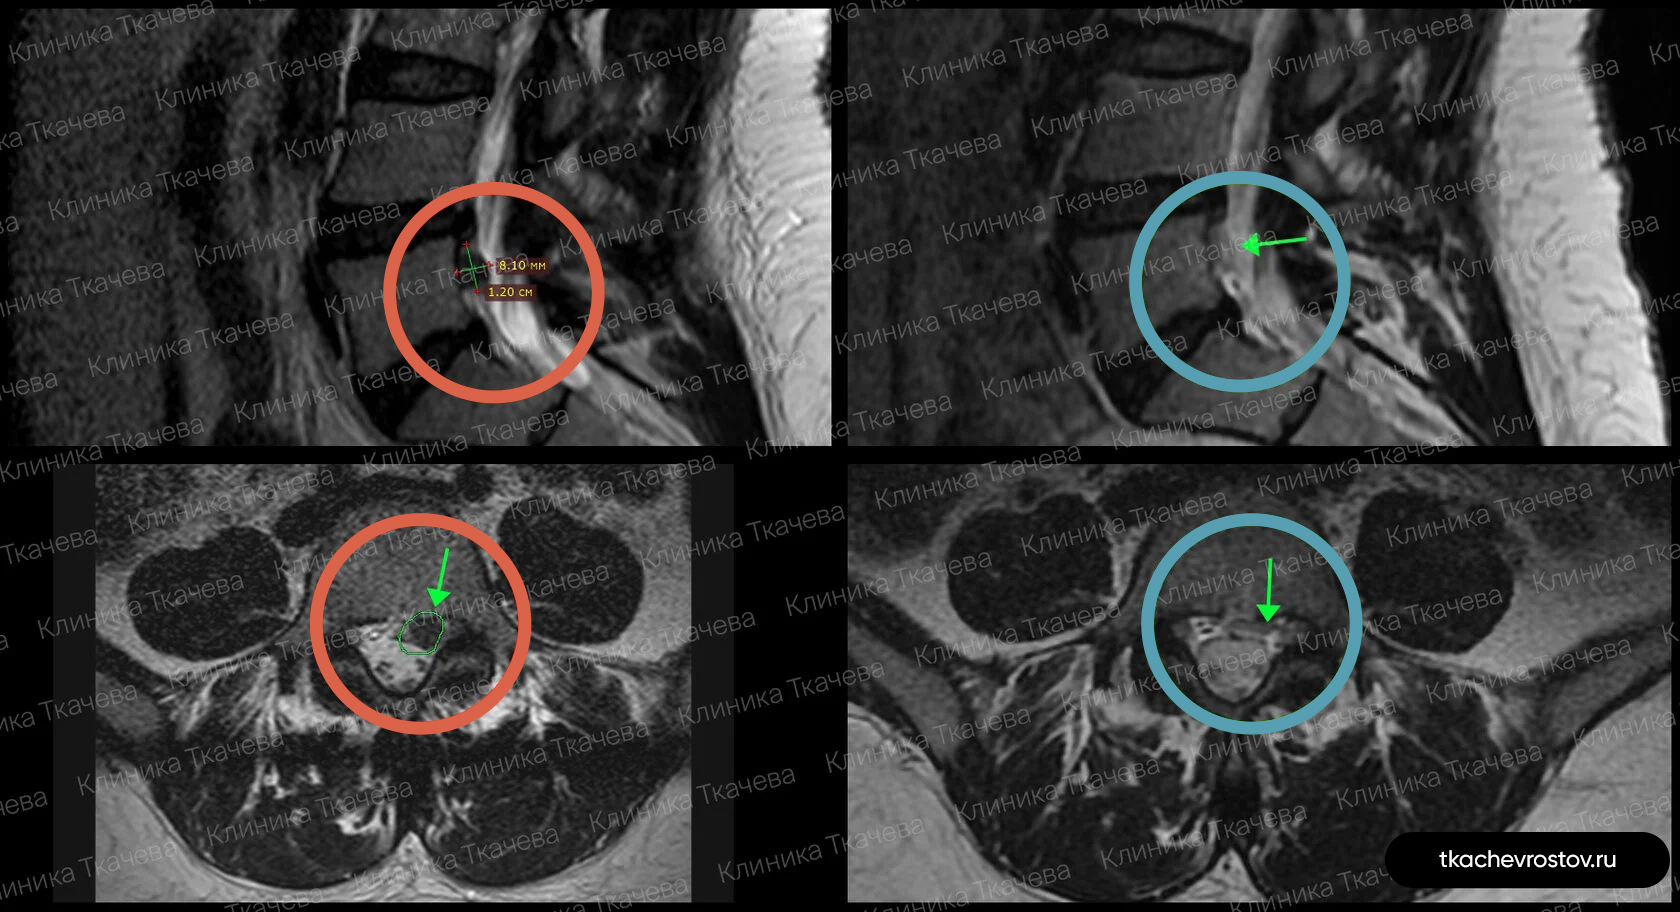

Грыжа в поясничном отделе L4-L5

Женщина. Грыжа в сегменте L4-L5 9 мм х 2 см. Невролог направлял на операцию, нейрохирург пугал отказом всех возможных систем жизнеобеспечения.

ДО:

- Боль в спине

- Онемение в левой ноге

- Снижение бытовой и социальной активности

ПОСЛЕ 1 курса:

✓ Наступила полная резорбция грыжи

✓ Наступило улучшения общего состояния.

ПОСЛЕ 2 курса:

✓ На 2022 всё стабильно.

Лечение грыжи заняло 5 месяцев. Было проведено 2 курса лечения.